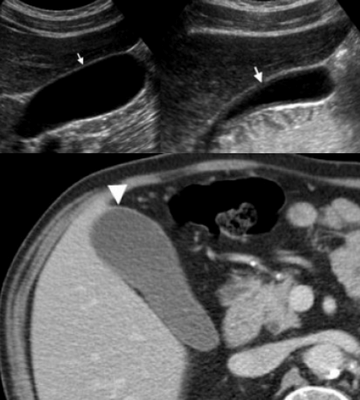

Слева — УЗИ — желчного пузыря у 59 летней женщины с острым холециститом. Субсерозный отек так, как гипоэхогенное утолщение между гиперэхогенными слоями (мышечным и слизистым). Справа — КТ брюшной полости с контрастным усилением. Также визуализируется субсерозный отек так, как наружный слой гиподенсный.

Острый калькулезный холецистит. После контрастного усиления визуализируется растянутый желчный пузырь (белые наконечники) со слегка утолщенной стенкой. Визуализируется камень в шейки желчного пузыря (белая стрелка).

Сверху изображения пациента 62 лет с калькулезным холециститом. На УЗИ визуализируется стенки желчного пузыря растянутые, с субсерозным отеком (указано белыми стрелками) и в просвете желчного пузыря камень и взвесь. На КТ визуализируется переход воспалительного процесса с желчного пузыря на соседние ткани (перихолецистит).

УЗИ (слева) и КТ (справа) желчного пузыря. На УЗИ ярко выраженное утолщение стенки желчного пузыря (указаны белыми стрелками). Множественные камни в просвете желчного пузыря (указано стрелкой). Компьютерная томография с контрастным усилением. На КТ визуализируются утолщение стенки с внутристеночными гиподенсными включениями. На КТ также выявлено, что процесс распространился на печень (указано стрелкой).